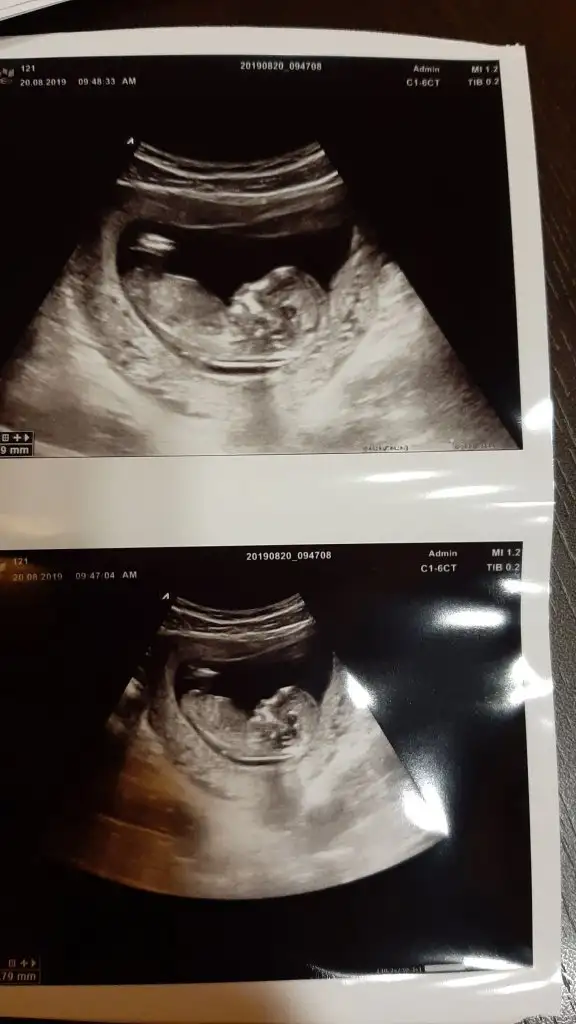

- 28 Ekim 2018

- 13

Kaç haftalık burda tam görünmüyor nub altı paralel geliyor yanılmıyorsam kız bu minnoşArkadaşlar merhaba ben de 13 haftalik hamileyim doktor yanilma payını düşünerek suan belirtmedi cinsiyetini yorumlarsaniz sevinirim. Tabi hic önemi yok cinsiyetin ama bir haftadir aşırı merak içindeyim:)) hepimize saglikla kucağına almayi nasip etsin

Canım teşekkürler öncelikle cevabin icin:) 13+3 o fotoğraftaKaç haftalık burda tam görünmüyor nub altı paralel geliyor yanılmıyorsam kız bu minnoş